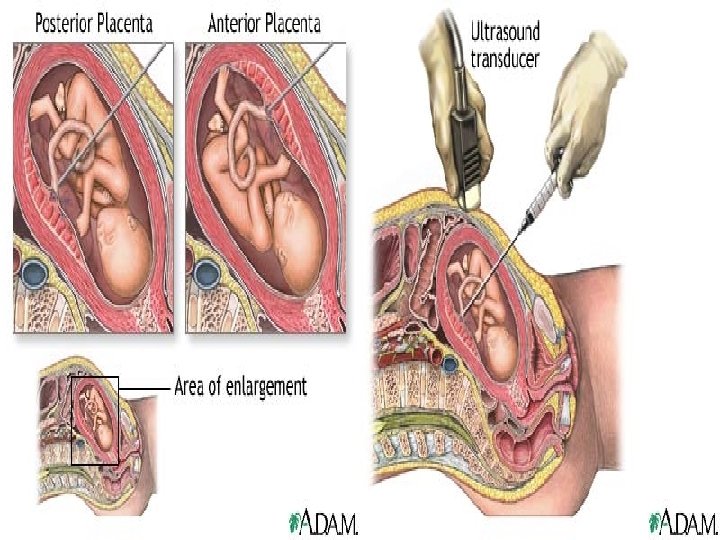

Percutaneous umbilical blood sampling Allow measurement of fetal; Hemoglobin Hematocrit Blood gases p. H Bilirubin level

Risk from PUBS: -Fetal exsanguination from placental vessels tear -fetomaternal hemorrhage 40%